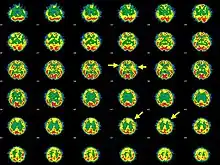

| Brain SPECT transaxial images of a patient afflicted with Hashimoto's encephalopathy. | |

- Single photon emission computed tomography shows focal and global hypoperfusion (75% of cases)